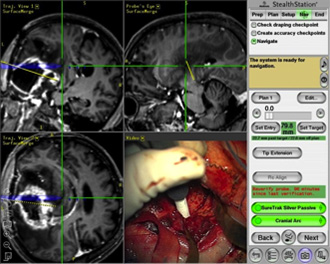

ニューロナビゲーション Neuronavigation

脳腫瘍の位置を手術中に知ることが出来ます。同時に脳の重要な機能部位もわかりますので、それらを損傷しないように手術を行うことが出来ます。